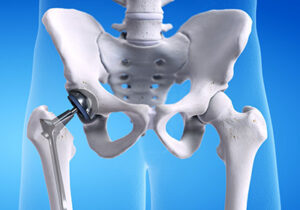

- Joint Replacement, Orthopedics And Sports Injury Specialist

- Fellowship in Joint Replacement & Sports Medicine

Expertise